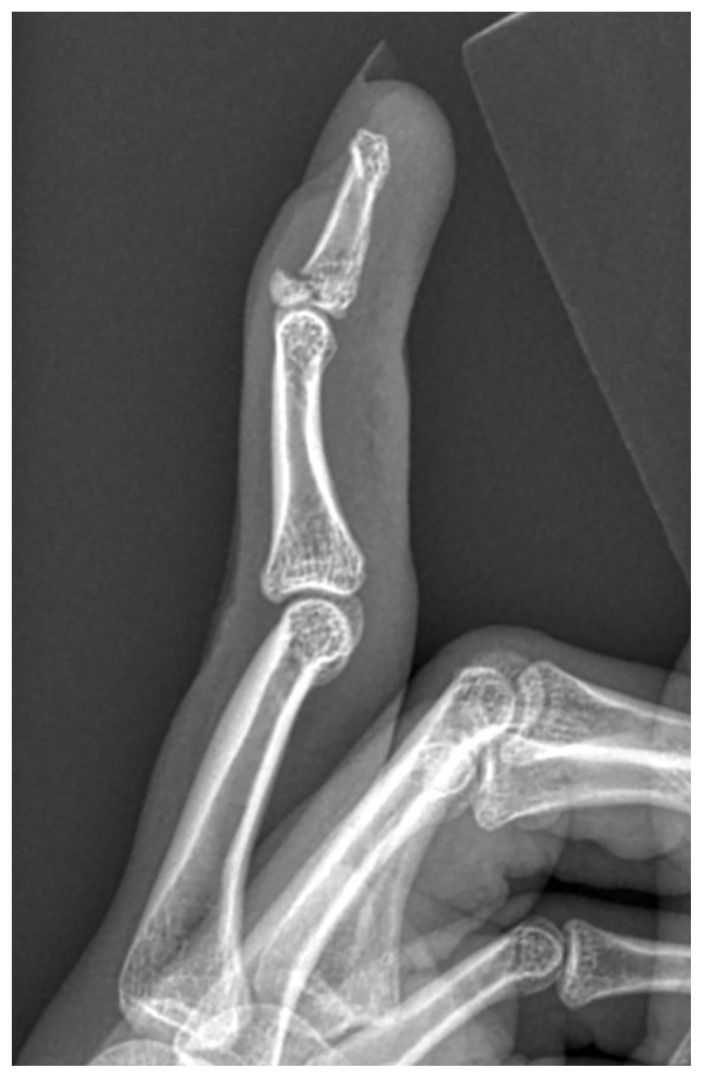

Mallet finger in a 19-year-old athlete.

一个19岁运动员的槌状手指。